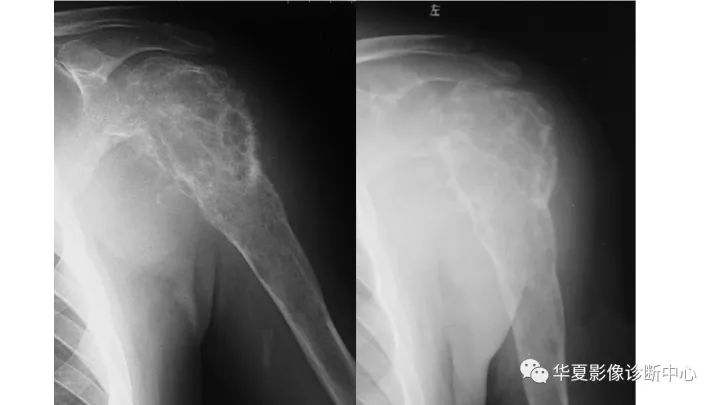

肱骨上段软骨肉瘤1例X线CT及MR影像表现

【病例】肱骨上段软骨肉瘤1例X线CT及MR影像表现